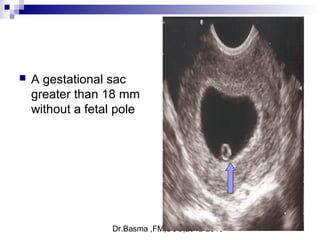

Signs suggestive of abnormal embryonic developmentSigns suggestive of abnormal embryonic development

 include a gestational sac greater than 10 mm10 mm in diameter without a visible

yolk sac

 gestational sac greater than 18 mm18 mm in diameter without a fetal pole

 a collapsed gestational sac

 A gestational sac

greater than 18 mm

without a fetal pole